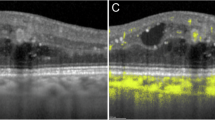

High resolution in situ transscleral 2-photon excitation fluorescence imaging (TPEF) further confirmed the effect of Lat-B on F-actin in the mouse aqueous drainage tissues, as shown in Fig. 8. In control mice, a curvilinear network of F-actin that was denser and more intense in the ciliary muscle than in the adjacent TM was seen. Following exposure to 10 μM Lat-B as a representative dose, F-actin labeling that was initially arranged as a curvilinear network rearranged as aggregates.

(A) F-actin labeling (red) of unperfused control eye (n = 3 mice). Ciliary muscle (CM) F-actin labeling is brighter and denser compared with adjacent trabecular meshwork (TM). Cortical F-actin organized as a curvilinear network is prevalent without punctate F-actin. (B) F-actin after Lat-B (10 μM, n = 3) delivery in live mice. The curvilinear F-actin network was absent but punctate F-actin was prominent. Closed arrows: Cortical F-actin organized as curvilinear network. Open arrows: Punctate F-actin. Dashed lines: CM-TM border. Insets: 2× magnification of sample region in the TM. Semi-transparent boxes: indicate region of TM selected for magnification in inset. Scale bar, 25 μm.